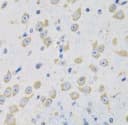

MSRA antibody

CAT:

710-FNab05382

Size:

100 µg